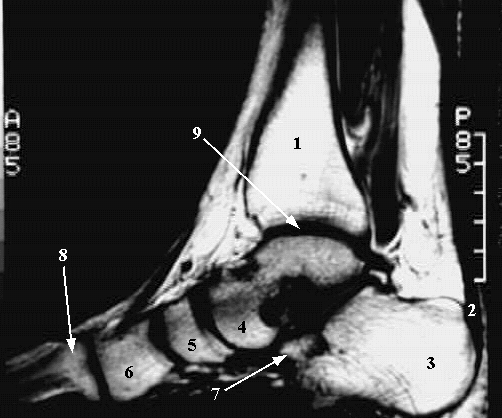

Lower Limbs: Ankle MRI Zoom

1. Lower end of tibia

2. Calcaneal tendon

3. Calcaneus

4. Talus

5. Navicular

6. Medial cuneiform

7. Sustentaculum tali

8. First metatarsal bone

9. Talocrural joint (ankle)